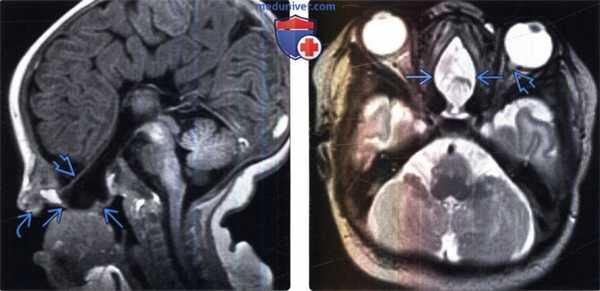

(Слева) Бесконтрастная КТ, аксиальный срез: у мальчика с объемным образованием глабеллярной области (лобно-носовое цефалоцеле) определяется отсутствие носовых костей и носовых отростков лобной кости, а также объемное образование ликворной интенсивности сигнала в глабеллярной области. Отмечается легкий гипертелоризм. Височный рог левого бокового желудочка расширен.

(Справа) МРТ, Т2-ВИ, сагиттальный срез: у этого же пациента определяется дефект кости рядом с лобно-носовым швом, содержащий объемное образование ликворной интенсивности сигнала. Такая картина согласуется с цефалоцеле. Наблюдается дисморфизм мозолистого тела.

(Слева) МРТ, Т1-ВИ, сагиттальный срез: у младенца с обструкцией полости носа определяется срединное базальное цефалоцеле, содержащее СМЖ, мозговые оболочки и, вероятно, обонятельные тракты. Обратите внимание на ассоциированную дисге-незию мозолистого тела, аномальное строение твердого неба и дисморфичный нос.

(Справа) МРТ, Т2-ВИ, аксиальный срез: у новорожденного с обструкцией полости носа обнаруживается крупное срединное базальное (клиновидно -решетчатое) эцефалоцеле. Обратите внимание на ассицированный заметный гипертелоризм и колобому слева, что предполагает синдром «ипомеи».